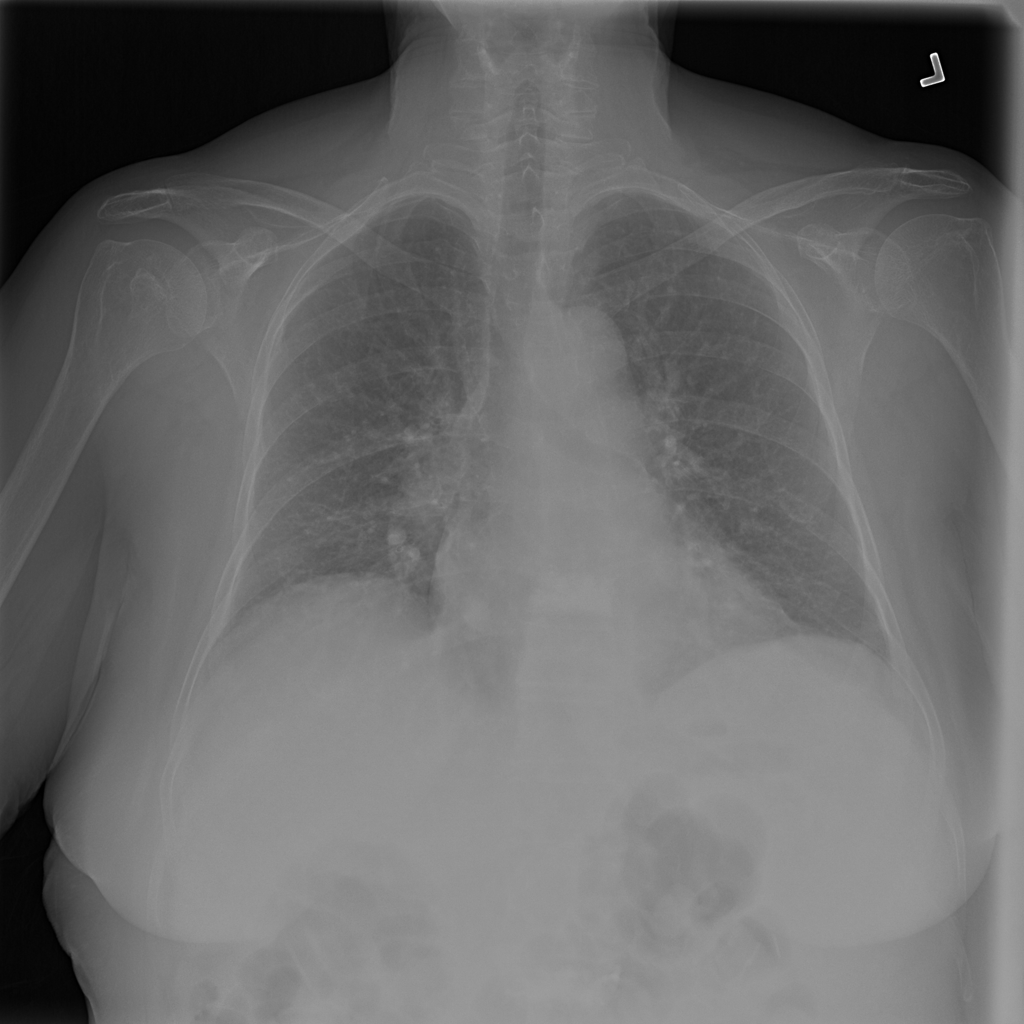

PAT-4639 · IMG-045Cardiomegaly

PAT-4639 · IMG-045

PA